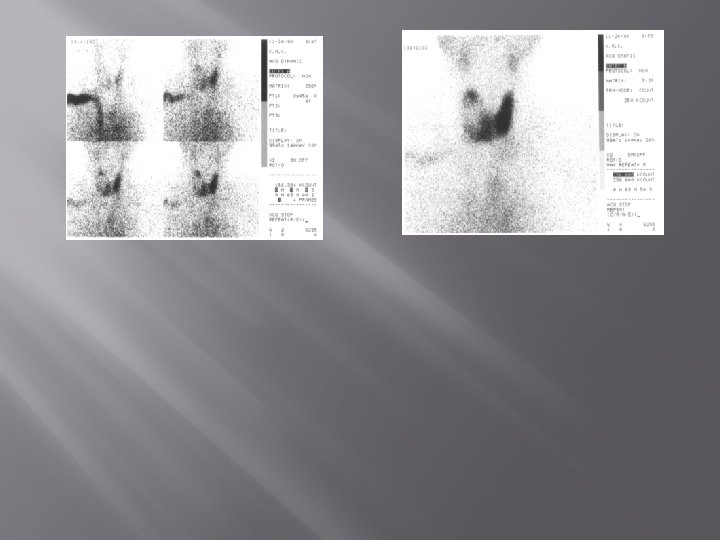

RADIOIODINE THERAPY Thyroid remnant Before ablated Thyroid remnant After ablated

1. Laki-laki 48 th post operasi total thyroidectomy karena malignansi thyroid. Sisa kelenjar thyroid yg sakit yang masih ada pada thyroid scan dengan TC-99 m 2. THYROID SCANN PRE RADIASI DAN POST RADIASI